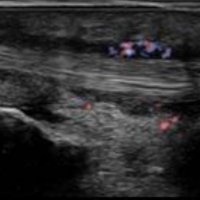

Thickening and hyper-vascularization of the A1 pulley are the hallmarks of trigger fingers on sonography. Other frequently observed features include distal flexor tendinosis and tenosynovitis.

The condition can be conservatively managed with splinting, NSAIDs, and local steroid injections or may require a surgical section of the A1 pulley when the pulley is markedly thickened.